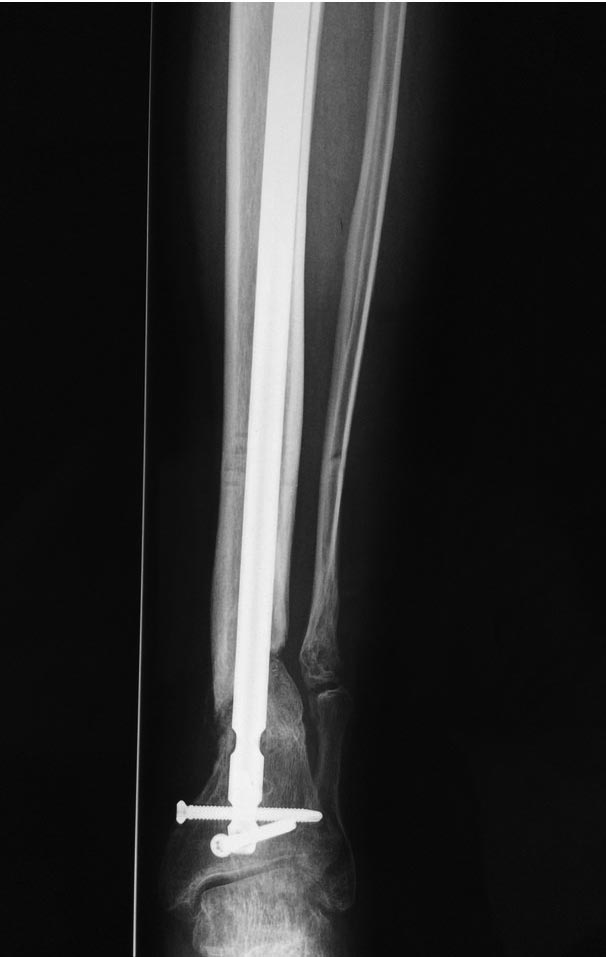

Уважаемые коллеги выразите Ваше мнение по следующему случаю.Молодой человек, 27 лет, находится на лечении с диагнозом: Ложный сустав большеберцовой кости в нижней трети, фиксированный интрамедуллярным блокированным стержнем (12.02.2014 г), ложный сустав малоберцовой кости в нижней трети левой голени, посттравматический артроз левого голеностопного сустава 1 стадии. Укорочение левой нижней конечности на 1,0 см. Со слов пациента известно, что в детстве получил перелом большеберцовой кости, лечился консервативно, перелом сросся с деформацией. Травма в июле 2010 г. бытовая-упал на лестнице, получил перелом малоберцовой кости, и перелом большеберцовой кости без смещения. Выполнена операция: Остеотомия большеберцовой кости в нижней трети, интрамедуллярный блокированный остеосинтез большеберцовой кости левой голени. Гладкое течение послеоперационного периода. Перелом большеберцовой кости сросся. Функция конечности восстановилась. В июне 2013 г выполнена операция удаление интрамедуллярного стержня из большеберцовой кости левой голени. Гладкое течение послеоперационного периода. Приступил к занятием физкультурой, бег. В августе 2013 г спрыгнул с автобуса, с чемоданом в руках, появилась резкая боль в левой голени. За медицинской помощью обратился через 7 дней, при обследовании выявлено: Рефрактура большеберцовой кости. Рекомендовано консервативное лечение в гипсовой повязке. В январе 2014 г. установлен диагноз: Ложный сустав большеберцовой кости в нижней трети, малоберцовой кости в нижней трети левой голени. Контрактура сгибательно - разгибательная левого голеностопного сустава. Посттравматический артроз левого голеностопного сустава 1 стадии. Укорочение левой нижней конечности на 1,0 см. В феврале 2014 г выполнил первым этапом: Фиксацию ложного сустава в АНФ с восстановлением осей сегментов. Через семь дней БИОС с рассверливанием. После операции - вальгус голеностопного сустава. Гладкое течение послеоперационного периода. Нагрузка по переносимости боли. Через 6 недель динамизация, через 2 недели стали мигрировать 2 фронтальных винта. Пытался подкрутить, пришлось удалить. Через 6 мес., контроль - линия ложного сустава прослеживается, но имеется периостальная костная мозоль. Не хватает стабильности.Вопрос что делать?Вариант № 1- выполнить реостеосинтез с рассверливанием КМК и на 12 мм диаметра гвоздь (стоит 11 мм)и убрать ротацию стопы руками одномоментно или одномоментно при помощи АНФ во время операции. Вариант № 2 выполнить удаление гвоздя, сделать все то же, что 6 месяцев назад, но с восстановлением анатомических взаимоотношений в голеностопном суставе.Вариант № 3 Двухэтапно, вторым этапом пластина на большеберцовую кость + костная пластика области не сращения.Вариант № 4 удаление гвоздя и лечение в КДА. Вопросы:1. Какой вариант оперативного лечения будет оптимальным в данном случае.2. При двухэтапной методике в дистальном отломке имеется канал от гвоздя, как направить гвоздь к наружному отделу дистального отломка большеберцовой кости. Есть опасения, что гвоздик может пойти по тому же каналу. Использовать поллер спицы или винты – сработают ли? И достаточна ли будет жесткость фиксации дистального отломка большеберцовой кости на гвоздике при 3 – 4 винтах при реостеосинтезе гвоздем.3. Нужен ли остеосинтез малоберцовой кости в нижней трети, с целью создания латеральной опоры. К сообществу за советом.

Александр Николаевич спасибо за ответ. Три снимка перед внешним видом конечности крайние. На одном из них левая стопа в положении внутренней ротации 15 градусов.